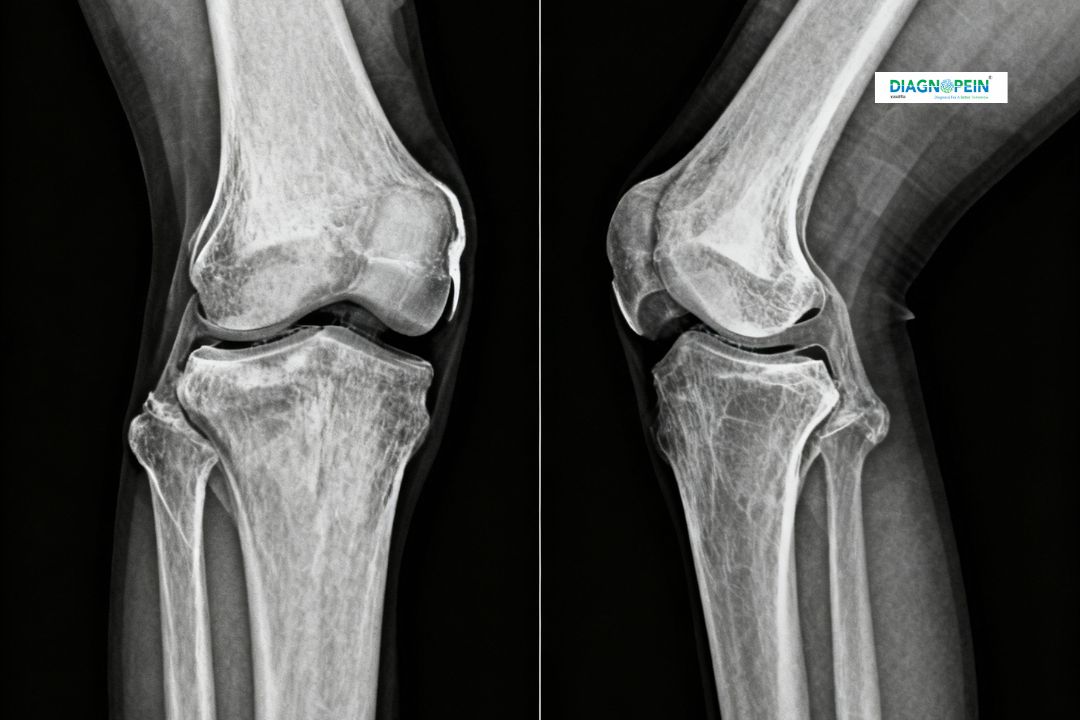

An X-Ray Left Knee AP / LAT (Anteroposterior and Lateral view) is a simple yet vital radiographic test that captures two images of the knee from different angles. This helps doctors assess bones, joint alignment, fractures, and degenerative changes.

The AP view shows the knee from front to back, while the lateral view gives a side angle image—together providing a complete picture of the left knee joint. At Diagnopein, Karad, we perform this test with modern digital radiography for the highest clarity and minimal radiation exposure.